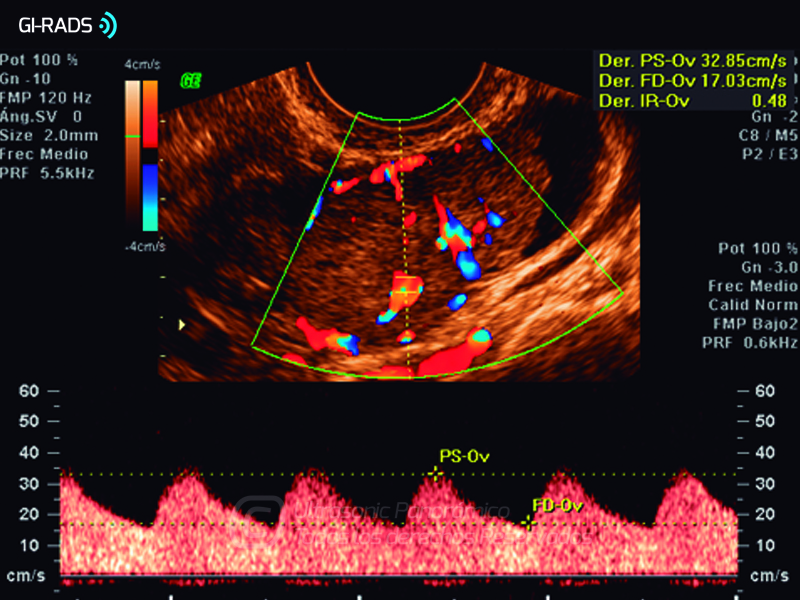

Cáncer Anexial – Baja Resistencia

• Cáncer Anexial – Baja Resistencia